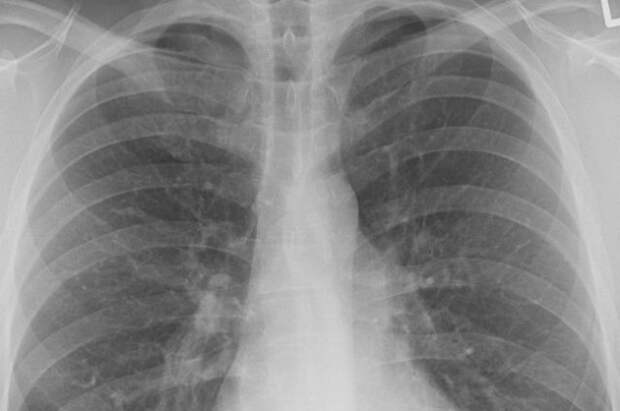

Баранова посоветовала при получении положительного результата на COVID-19 при отсутствии симптомов сделать томографию легких.